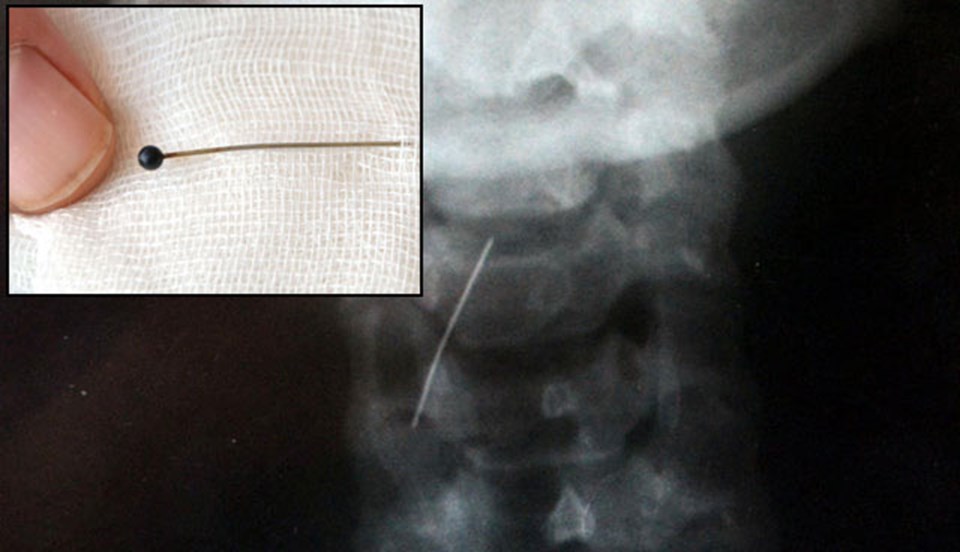

Burdur Devlet Hastanesi Göğüs Cerrahisi Uzmanı Op. Dr. Oktay Aslaner, genç kızın soluk borusuna yerleşen toplu iğneyi yaklaşık bir saat süren operasyonla aldı.

Aslaner, "İğne ses tellerinin altına gömülmüştü. Herhangi bir ameliyat yapılmadan endoskopik olarak çıkarttık" dedi.